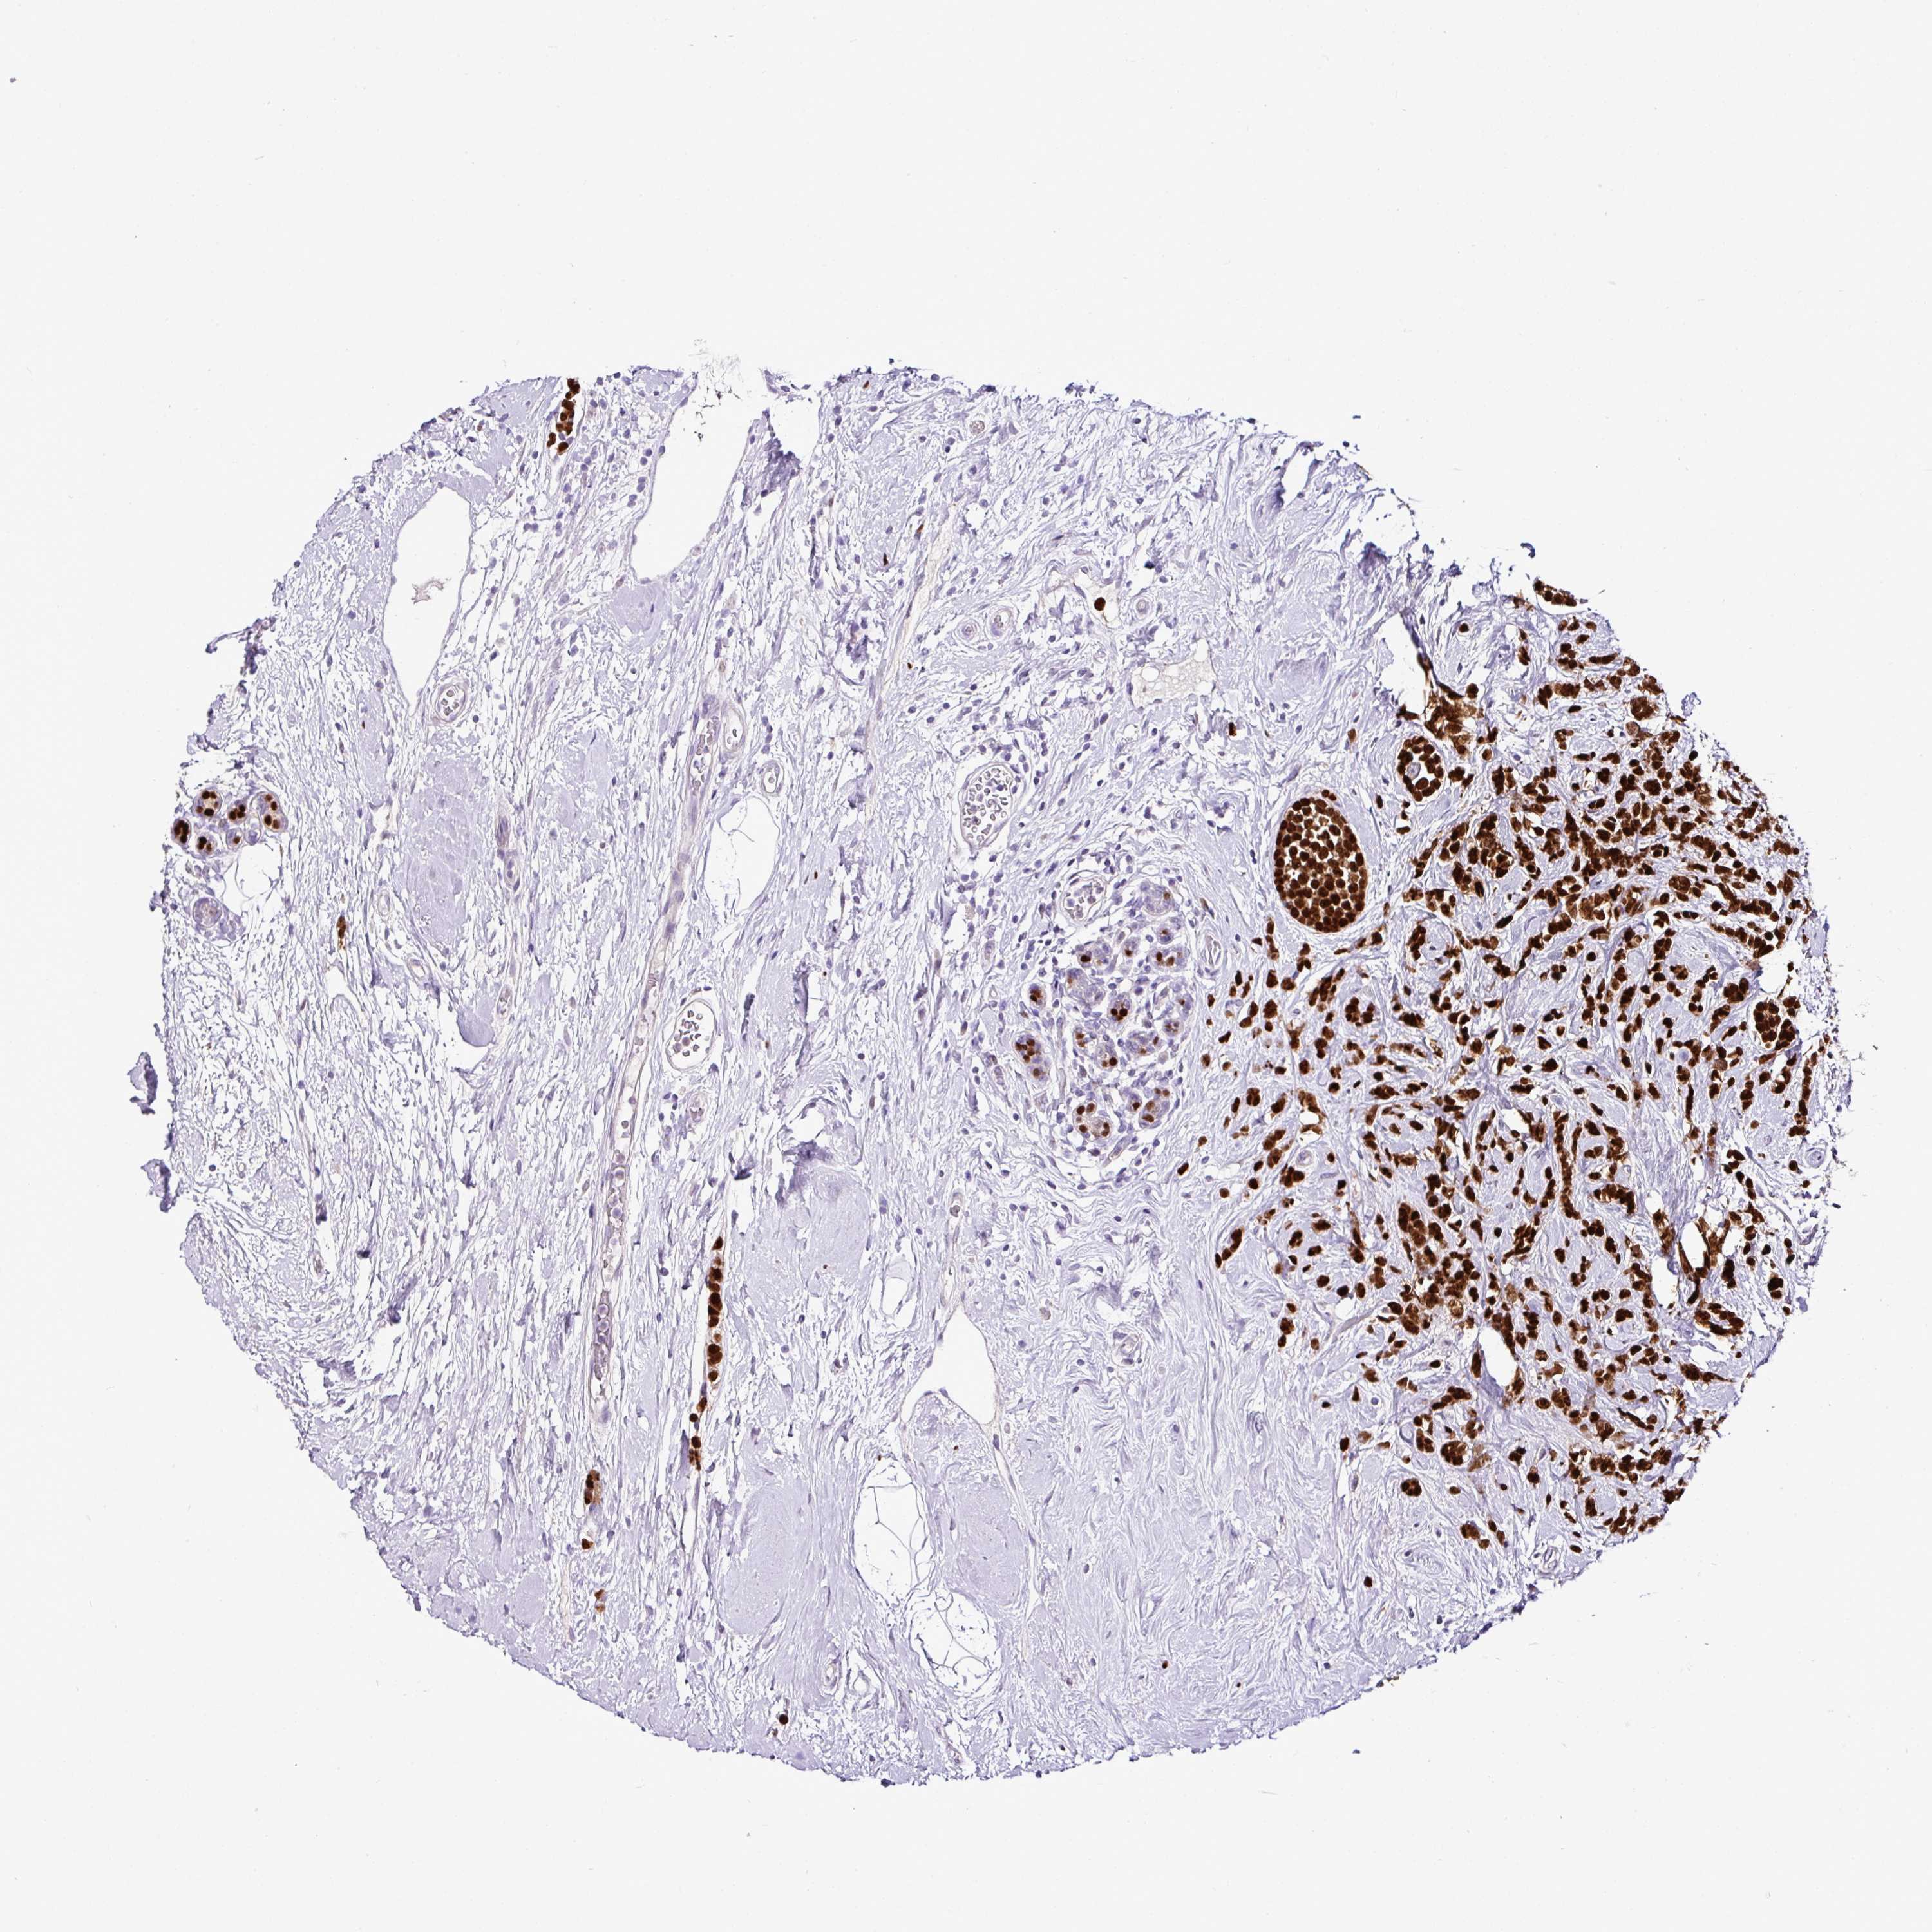

CANCER BREAST CANCER Show tissue menu

BRCA TCGA BRCA VALIDATION PROTEIN EXPRESSION

Breast cancer

Human cancer